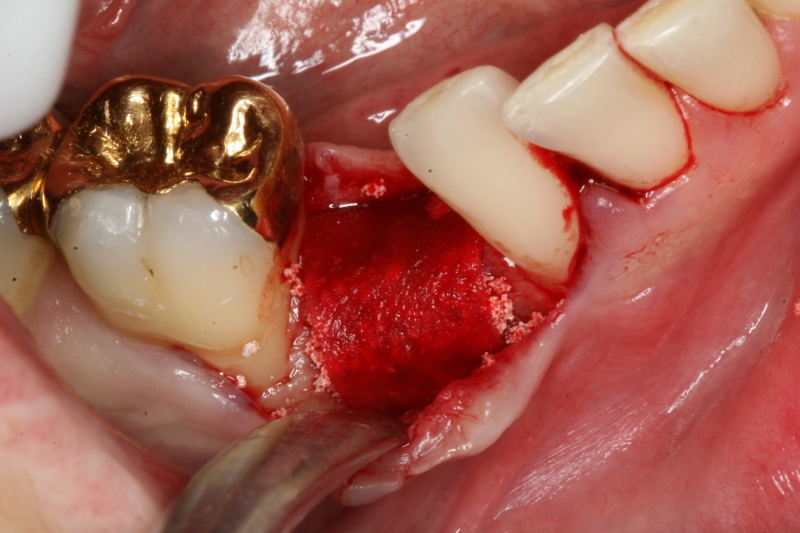

Initial situation: Inflammated tooth #12

Pre-surgical probing reveals a deep intrabony defect on the distal aspect of the upper canine.